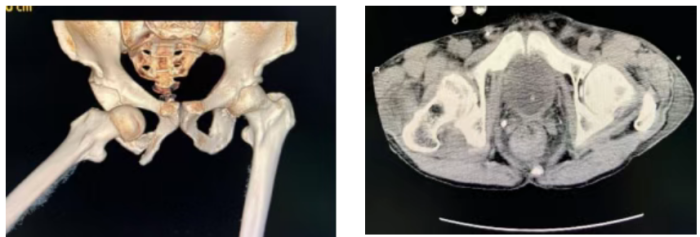

针对患者右侧髋臼脱位及骨盆骨折情况,急诊外科骨创伤团队率先为其实施急诊髋臼脱位手法复位牵引固定手术,并积极稳定循环,避免病情进一步恶化,为后续综合治疗奠定坚实基础。待患者生命体征趋于平稳后,急诊外科负责人申梓玄会同急诊外科团队,结合患者病情制定个性化微创治疗方案,决定采用超声引导下微创肋骨骨折内固定技术,为患者实施进一步治疗。与传统开放手术相比,该技术具有创伤小、出血少、恢复快、并发症少等显著优势,是医院急诊外科补齐技术短板、提升创伤救治水平的重要突破。